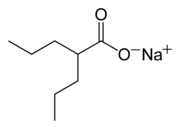

| Other names | Valproic acid; Sodium valproate (sodium); Valproate semisodium (semisodium); 2-Propylvaleric acid |

| Chemical and physical data | |

| Formula | C8H16O2 |

| Molar mass | 144.211 g·mol−1 |

Valproate's precise mechanism of action is unclear.[1][5] Proposed mechanisms include affecting GABA levels, blocking voltage-gated sodium channels, and inhibiting histone deacetylases.[6][7] Valproic acid is a branched short-chain fatty acid (SCFA) made from valeric acid.[6]

Valproic acid (VPA) is an organic weak acid. The conjugate base is valproate. The sodium salt of the acid is sodium valproate and a coordination complex of the two is known as valproate semisodium.[14]

Valproic acid is a branched short-chain fatty acid and a derivative of valeric acid.[6]

| Formula | C8H15NaO2 |

| Molar mass | 166.196 g·mol−1 |